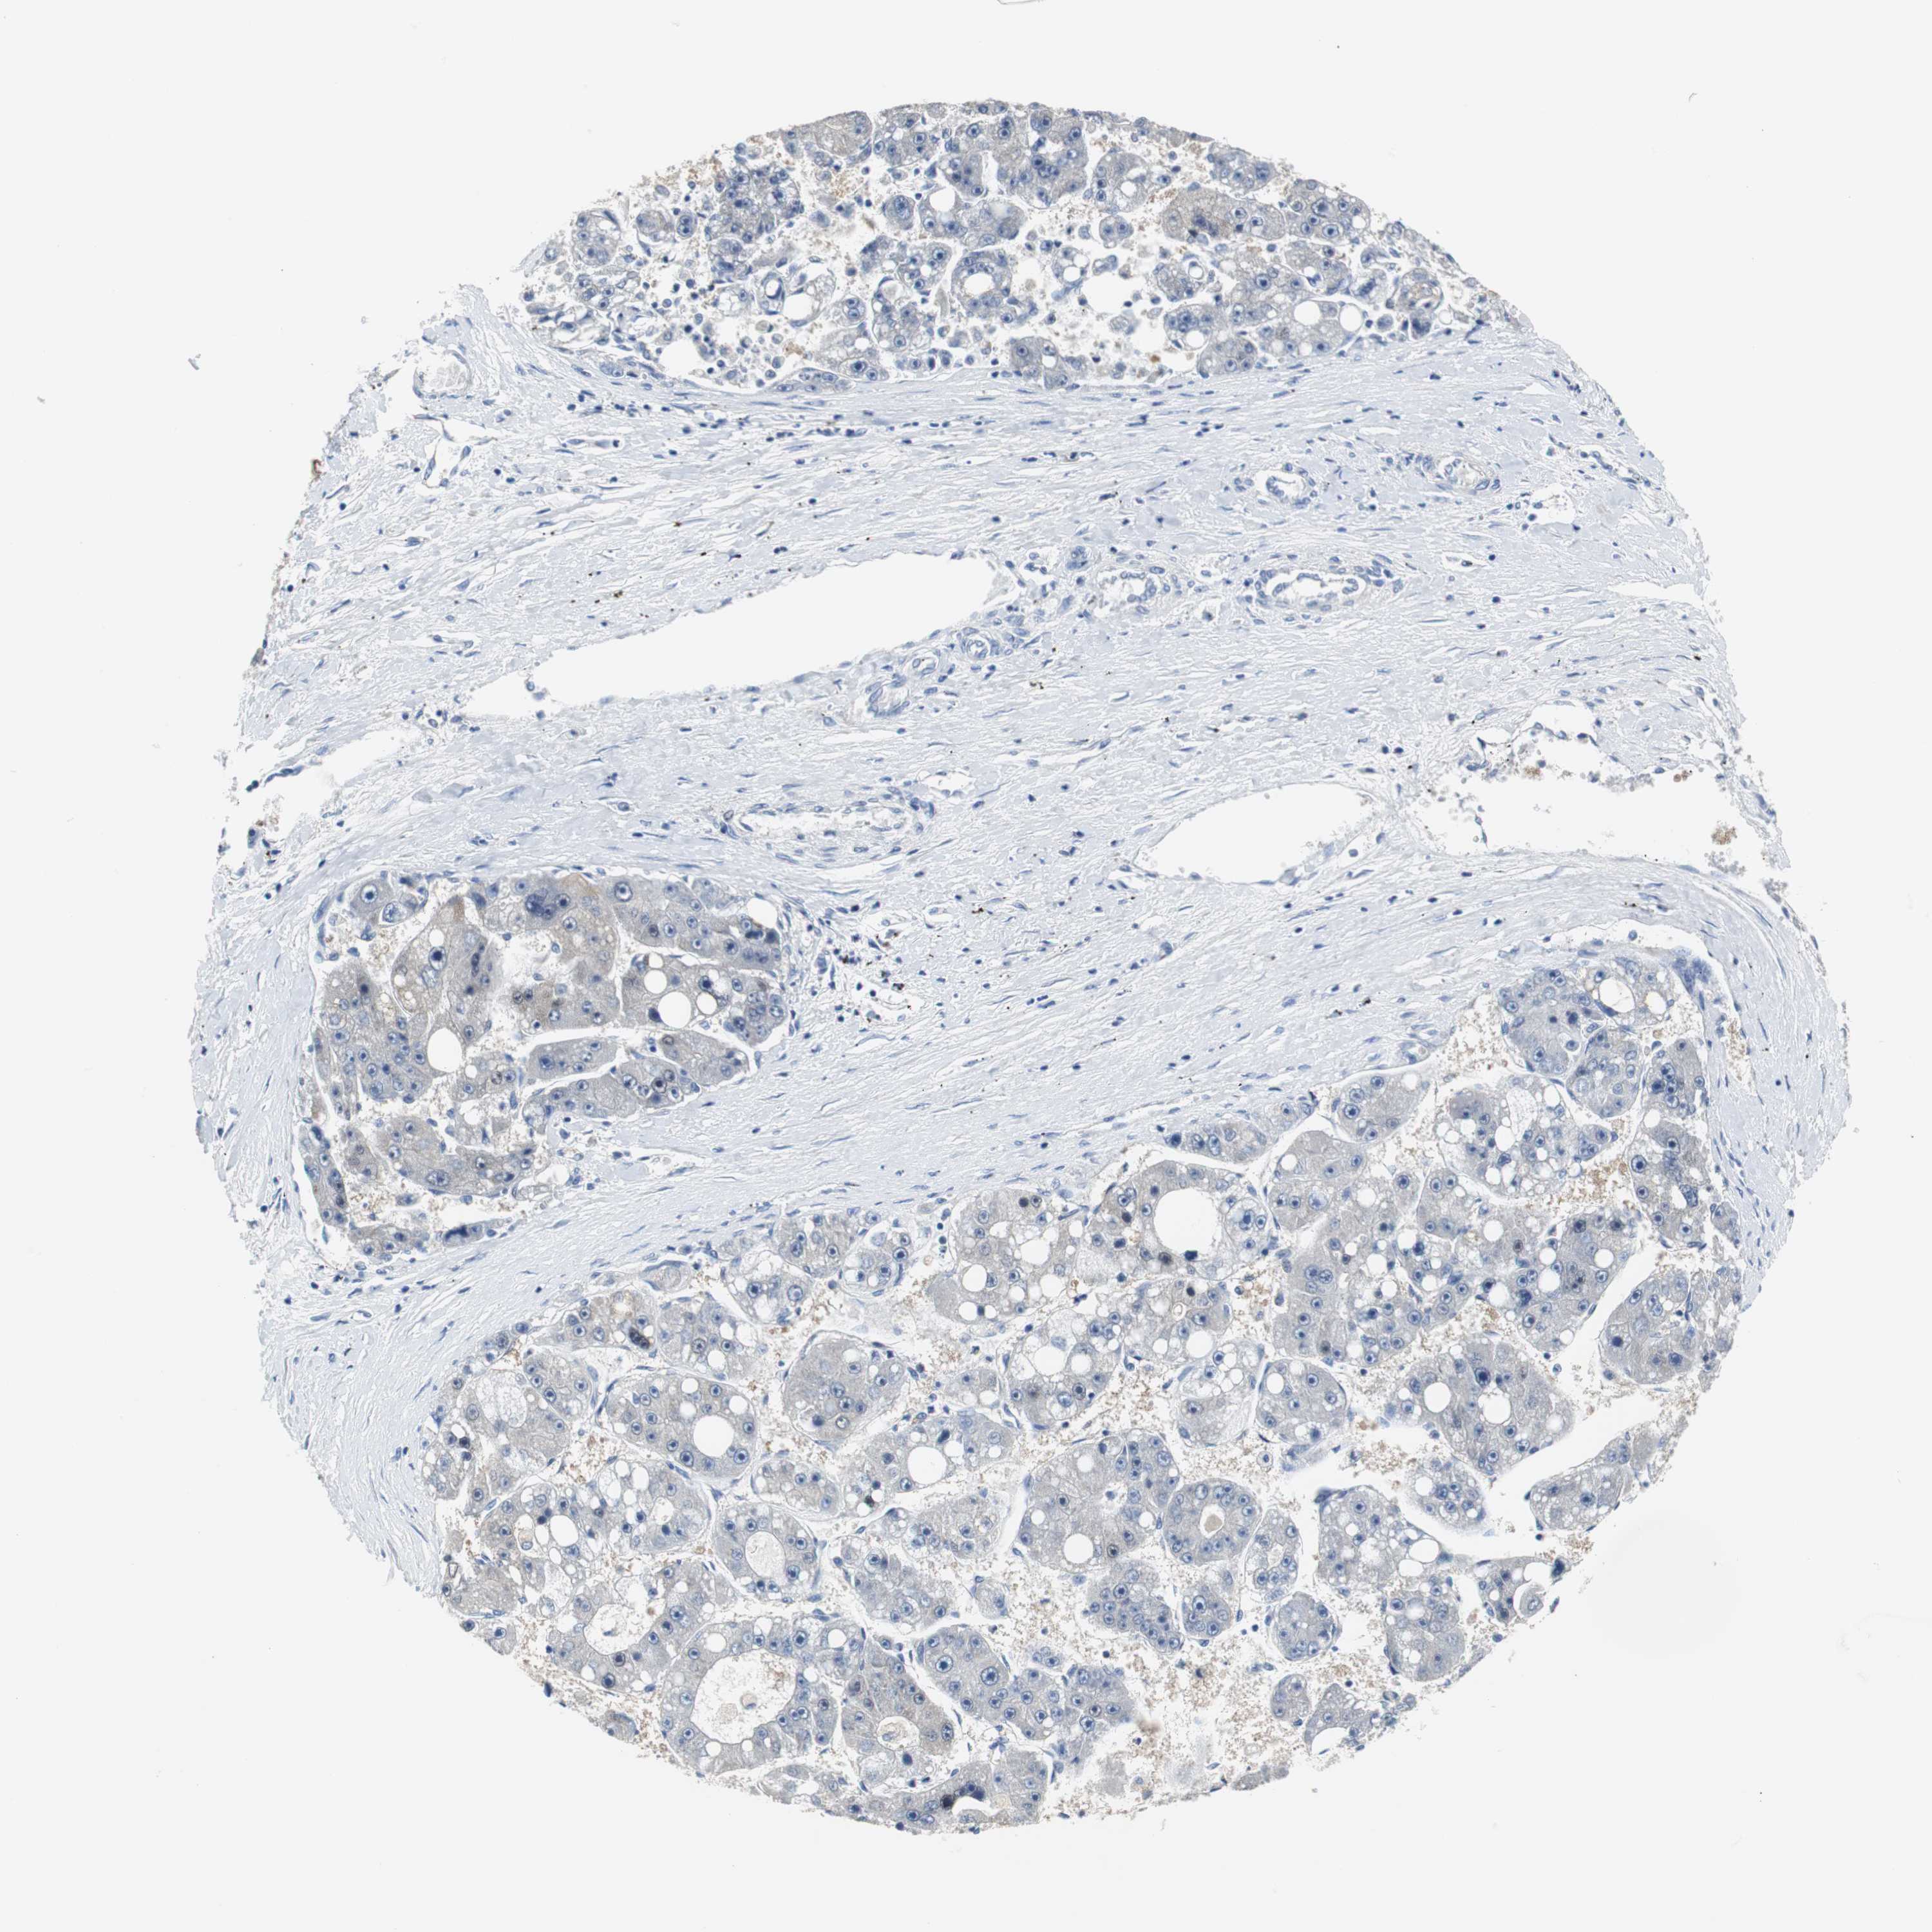

LIVER CANCER - Protein expressioni

A mouse-over function shows sample information and annotation data. Click on an image to view it in a full screen mode. Samples can be filtered based on level of antibody staining by selecting one or several of the following categories: high, medium, low and not detected. The assay and annotation is described here.

Note that samples used for immunohistochemistry by the Human Protein Atlas do not correspond to samples in the TCGA dataset.

Antibody stainingi

Antibody staining in the annotated cell types in the current human tissue is reported as not detected, low, medium, or high, based on conventional immunohistochemistry profiling in selected tissues. This score is based on the combination of the staining intensity and fraction of stained cells.

Each image is clickable and will lead to virtual microscopy that enables deeper exploration of all samples and also displays staining intensity scores, fraction scores and subcellular localization as well as patient and tissue information for each sample.

Antibody HPA006277

Antibody HPA006507

Antibody CAB017027

Staining

High

Medium

Low

Not detected

Intensity

Strong

Moderate

Weak

Negative

Quantity

>75%

75%-25%

<25%

None

Location

Nuclear

Cytoplasmic/membranous

Cytoplasmic/membranous,nuclear

Cholangiocarcinoma

Carcinoma, Hepatocellular, NOS